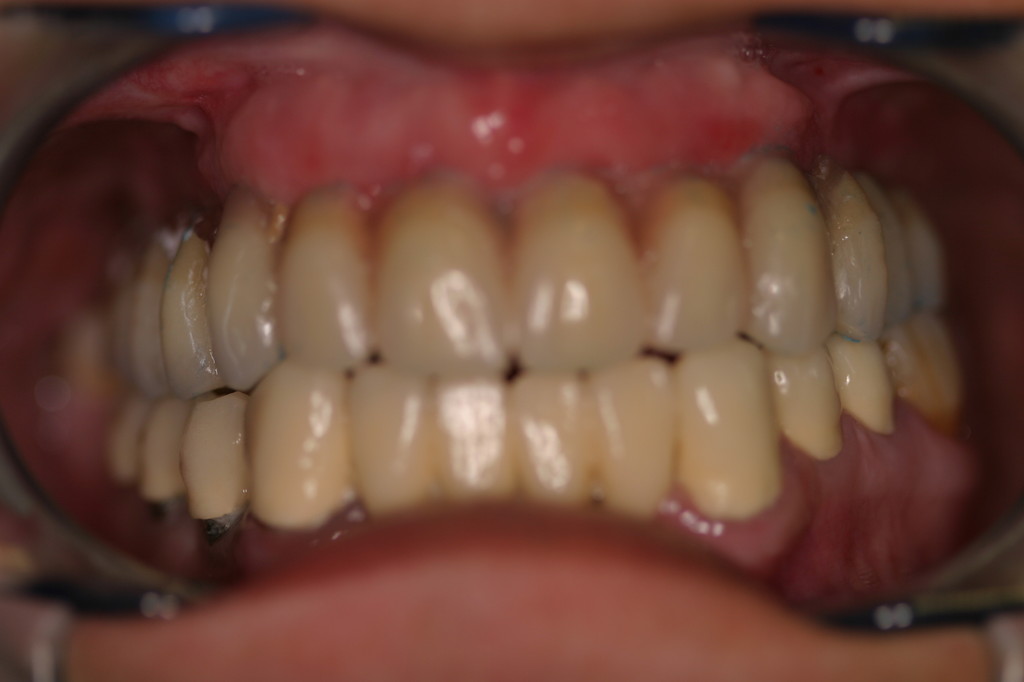

REHABILITACIÓN CON IMPLANTES Y CIRUGÍA PLASTICA PERIODONTAL.

REHABILITACIÓN CON IMPLANTES SIN CIRUGÍA.

REHABILITACIÓN CON IMPLANTES ,ENFERMEDAD PERIODONTAL AVANZADA.

REHABILITACIÓN IMPLANTOSORTADA EN MANDÍBULA Y MAXILAR.

REHABILITACIÓN ESTÉTICA CON IMPLANTES.